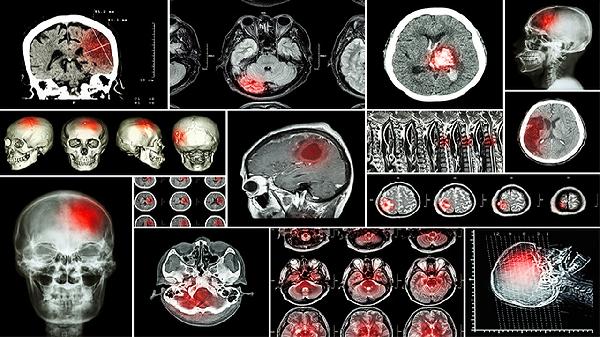

1、颅骨修补手术的目的:颅骨修补主要用于修复因外伤、手术或疾病导致的颅骨缺损,恢复颅腔完整性,保护脑组织,并改善外观。手术通常使用钛网、自体骨或3D打印材料进行修补。术后,患者需遵医嘱进行定期复查,确保修补部位愈合良好。